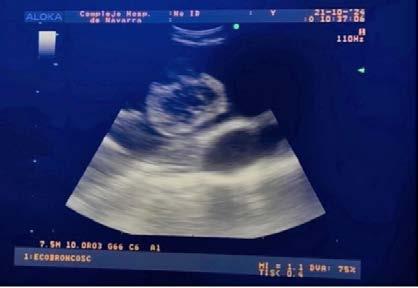

TROMBOEMBOLISMO VENOSO ASOCIADO A CÁNCER. Casos finalistas ..............................................................................................121

DEL HALLAZGO INCIDENTAL AL MANEJO

DEL TROMBO TUMORAL: EBUS EN EL DIAGNÓSTICO PRECOZ DE TROMBOEMBOLISMO..................................

Ana José Martín Serrablo. MIR Neumología. HUN.

Roger Antoni Frigola Castro. MIR Cirugía Vascular. HUN.

Enara Echauri Carlos. MIR Medicina Interna. HUN.